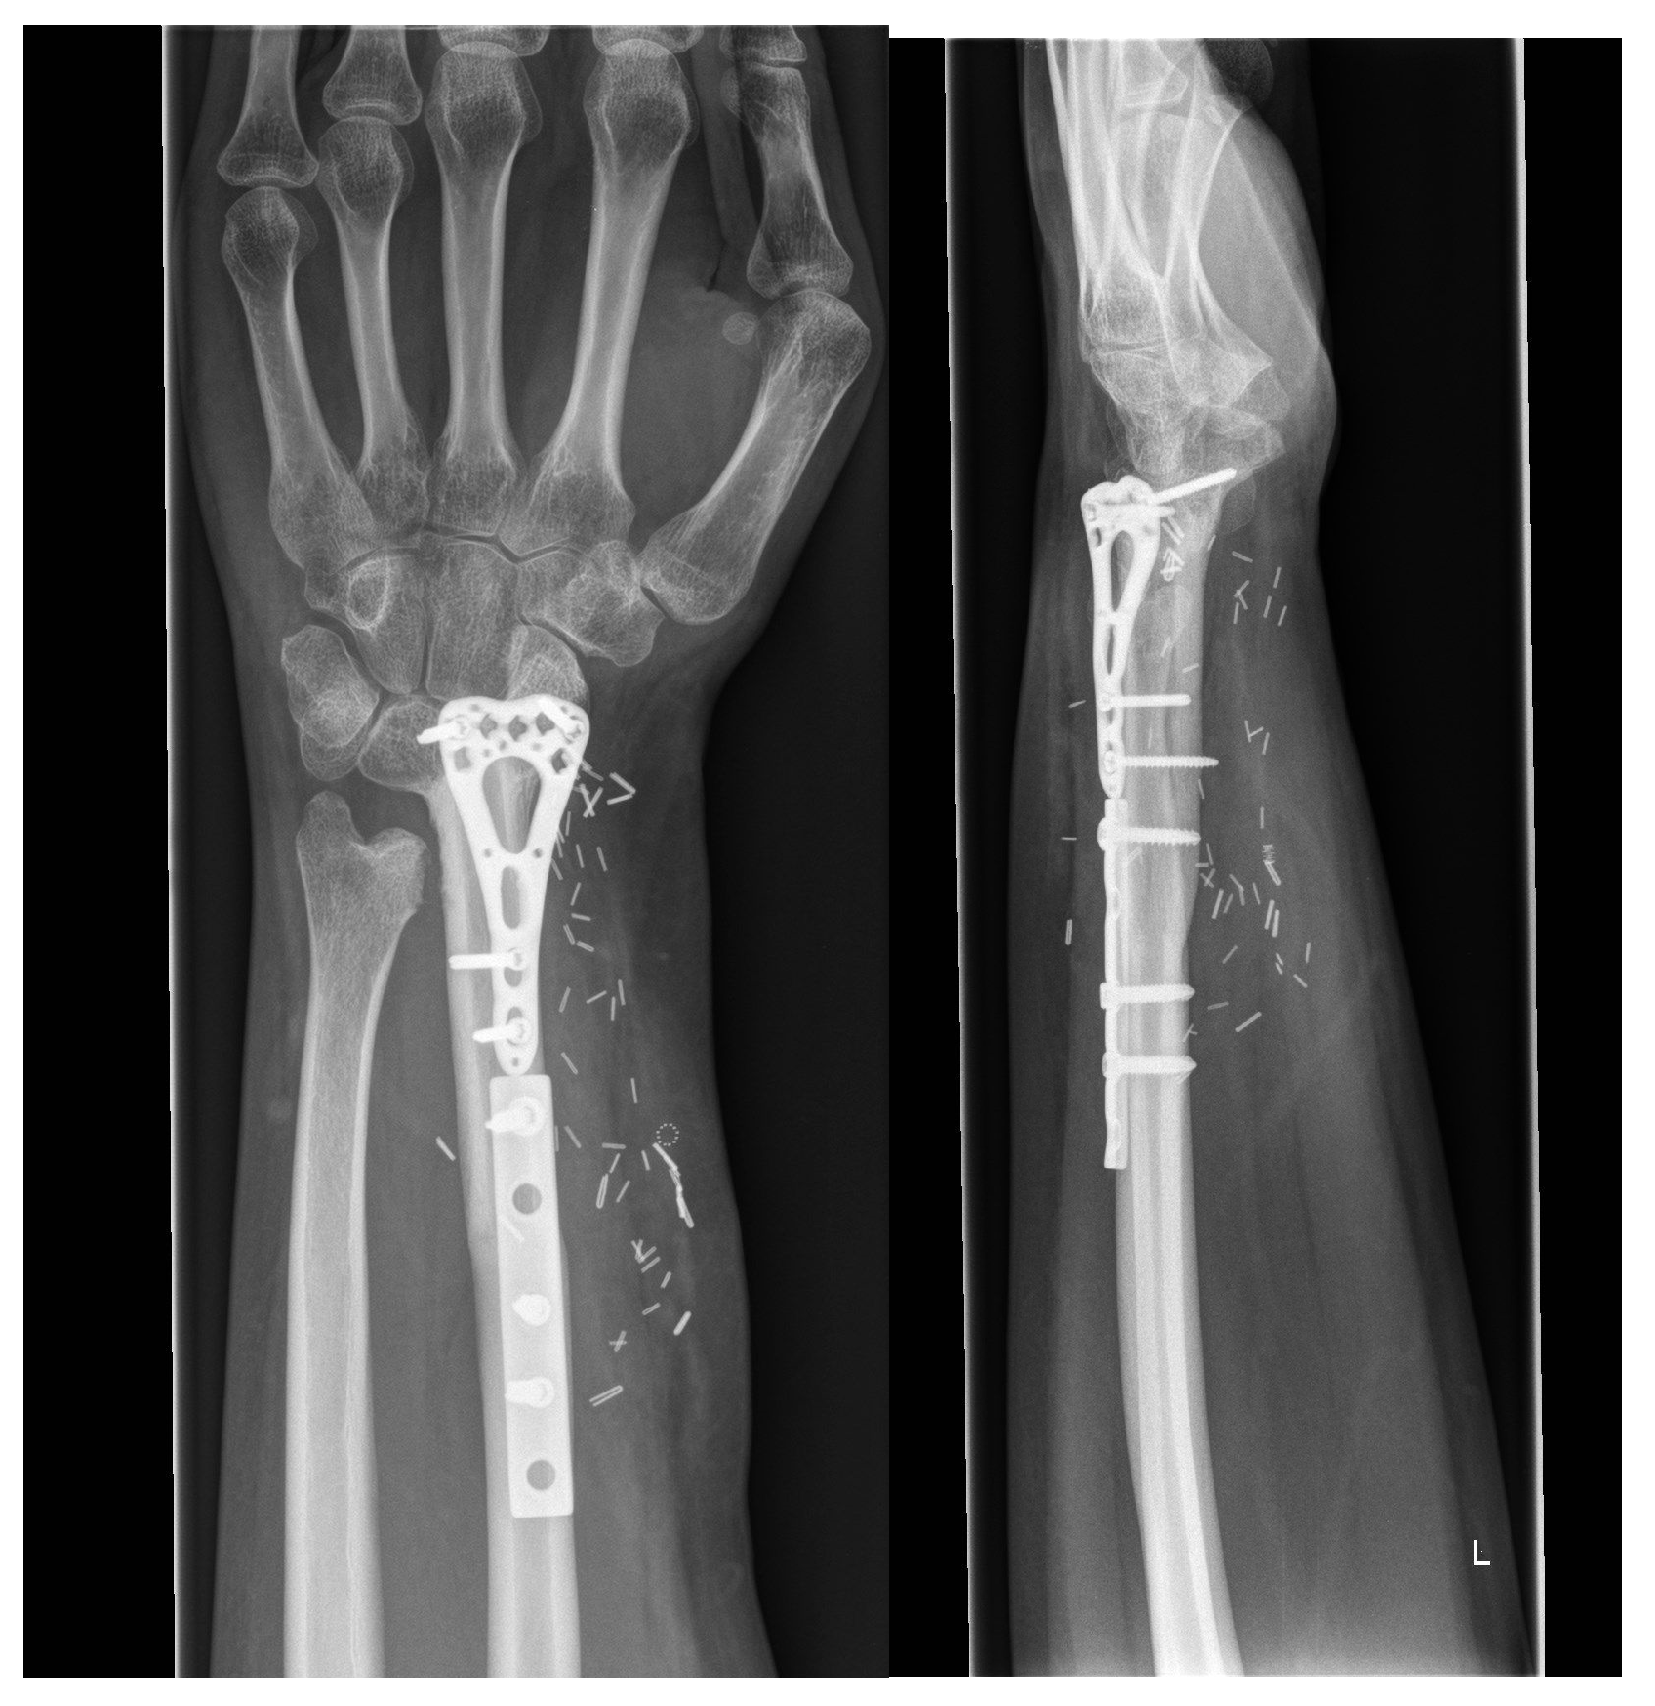

5.5. Group 4: Fusion of the Proximal Row of the Wrist with the Distal Radius (RFSL Fusion)

| GROUP 4 | Case 5 | Distal radius involving the radiocarpal surface | Sarcoma, secondary osteoblastoma | 61 | 20 | 9 | Vascularized fibula | RFSL-Fusion | N/A N/A | 25-0-30 50-0-60 | 70% | MMWS = 65 DASH = 24 | yes |

| Case 6 | Distal radius involving the radiocarpal surface | Giant cell tumor | 72 | 45 | 6 | Vascularized fibula | RFSL-Fusion | 60-0-60 70-0-70 | 30-0-30 70-0-50 | 80% | (N/A) | yes | |

| Case 7 | Distal radius involving the radiocarpal surface | Giant cell tumor | 25 | 38 | 8 | Vascularized fibula | RFSL-Fusion | 50-0-50 90-0-50 | 40-0-0 80-0-70 | 80% | (N/A) | yes | |

| Case 8 | Distal radius involving the radiocarpal surface | Giant cell tumor | 6 | 40 | 7.5 | Vascularized fibula | RFSL-Fusion | 70-0-70 80-0-80 | 30-0-10 50-0-50 | 60% | (N/A) | yes |